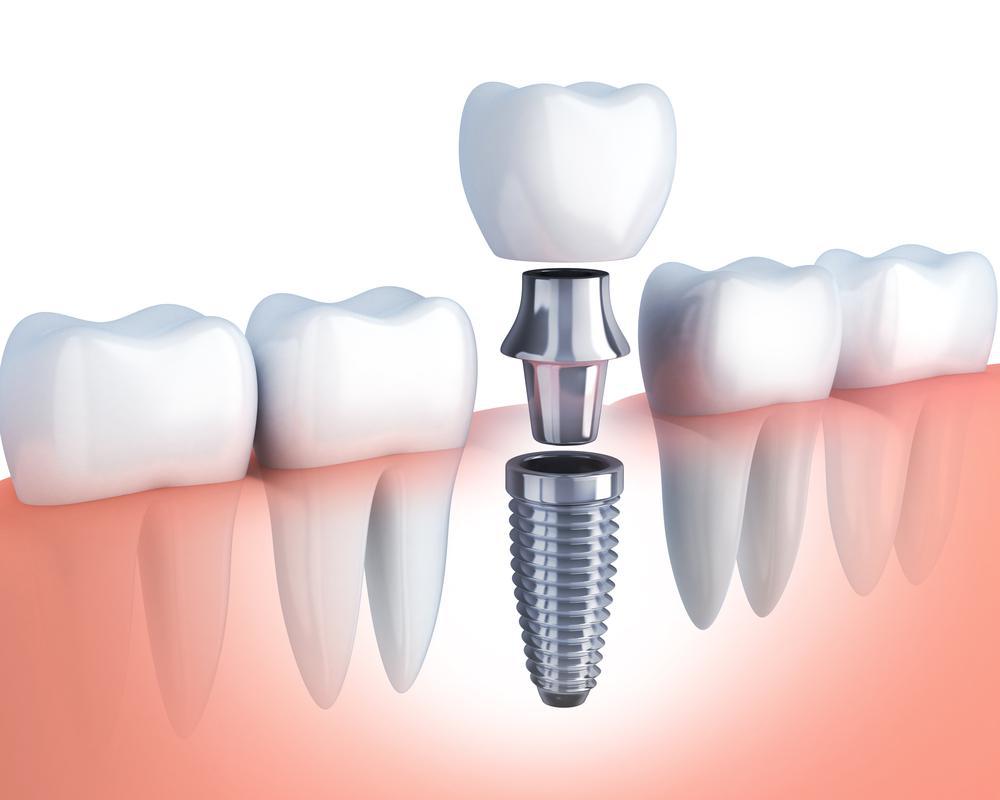

این روش مجموعهای از قطعات مختلف را شامل میشود که ۳ قطعه اصلی آن یعنی فیکسچر (پایه)، اباتمنت و تاج آن همیشه همراه شما هستند. علاوه بر این قطعات دائمی اجزای موقتی نیز در طی تکمیل فرایند کاشت ایمپلنت استفاده میشوند که پس از مدتزمان مشخصی از دهان خارج میشوند.

این روش مجموعهای از قطعات مختلف را شامل میشود که ۳ قطعه اصلی آن یعنی فیکسچر (پایه)، اباتمنت و تاج آن همیشه همراه شما هستند. علاوه بر این قطعات دائمی اجزای موقتی نیز در طی تکمیل فرایند کاشت ایمپلنت استفاده میشوند که پس از مدتزمان مشخصی از دهان خارج میشوند.

طی عمل جراحی پایه فلزی از جنس تیتانیوم کاملاً سازگار با بدن، در استخوان فک نصب میشود سپس با گذشت چند ماه و جوشخوردن آن به استخوان طی ۳ تا ۶ ماه، ادامه پروسه درمان ازسرگرفته میشود. این مرحله Osseo integration نام دارد که بسیار نقش مهمی در تکمیل مراحل ایمپلنت دندان ایفا میکند. پس از اتصال کامل پایه به استخوان و محکمشدن آن، تاجهای دائمی بر روی آن قرار میگیرد و فرد پس از دوره کوتاهی کاملاً میتواند عملکرد طبیعی خود را ادامه دهد.